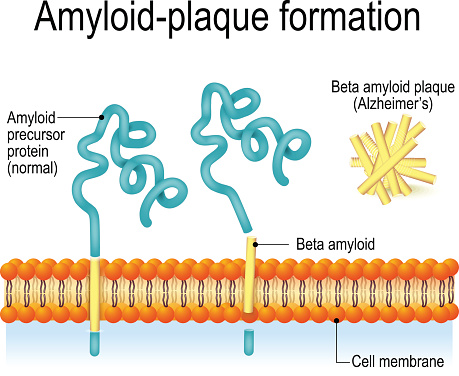

Alzheimer’s & Brain Awareness Month: Alzheimer’s disease and sleep disorders, hallucinations, Alzheimer’s prevention

June marks the beginning of sunshine-filled days and outdoor activities, but it also happens to be Alzheimer’s and brain awareness month. This is a time where the health community bands together to raise awareness about Alzheimer’s disease and other forms of dementia. At Bel Marra, we want to do our part, so we have provided ...click here to read more